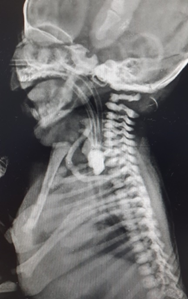

On examination, heart rate was 147/min, blood pressure was 75/50 mmHg, and respiratory rate was 52/ min, SPO2 was 97% with oxygen and capillary refilling time was <3 sec. with chest retraction. She had moderately increased secretions from mouth with bilateral conducted sounds. Feeding tube could not be negotiated into stomach. X ray showed coiling of infant feeding tube and large radiopaque shadow in the upper esophagus (Figure 1). Fact that child had accepted feeds well for initially 3 days without any discomfort, raised doubt in it being esophageal atresia. Contrast study was done which revealed large opacity from T2-4and trickling of contrast in stomach ruling out EA and esophageal perforation (Figure 2).

Figure 1 X ray showed coiling of infant feeding tube and large radiopaque shadow in the upper esophagus.